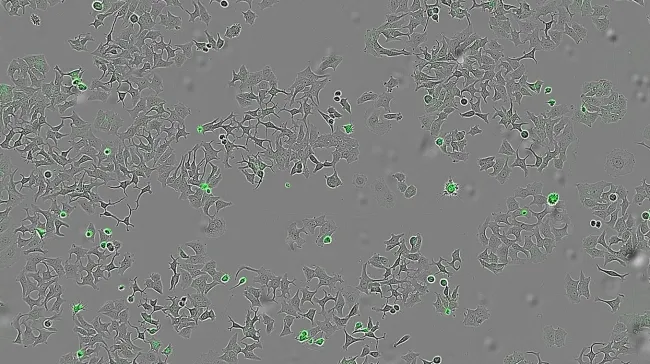

Now playing Next Zdravlje Španski naučnici otkrili protein koji može natjerati ćelije raka na samouništenje